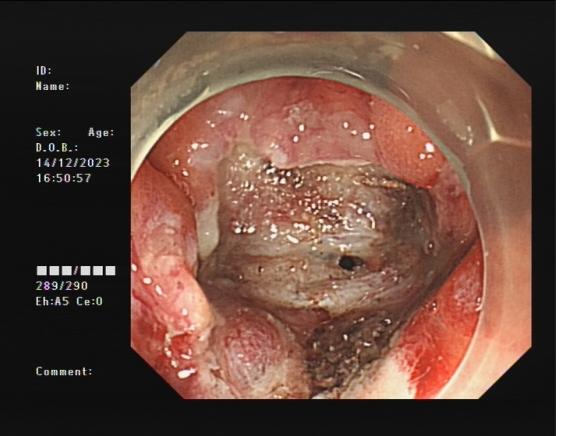

0d0b80a96701483cbcbf8b67351feac3.Jpeg8f7177645651428ca3a0f3c87dfd559d.Jpeg

直腸側(cè)向發(fā)育性腫瘤      內(nèi)鏡下黏膜下剝離術(shù)后創(chuàng)面

內(nèi)鏡下黏膜剝離術(shù)(ESD):治療巨大平坦息肉,早期癌及癌前病變,黏膜下腫瘤等。